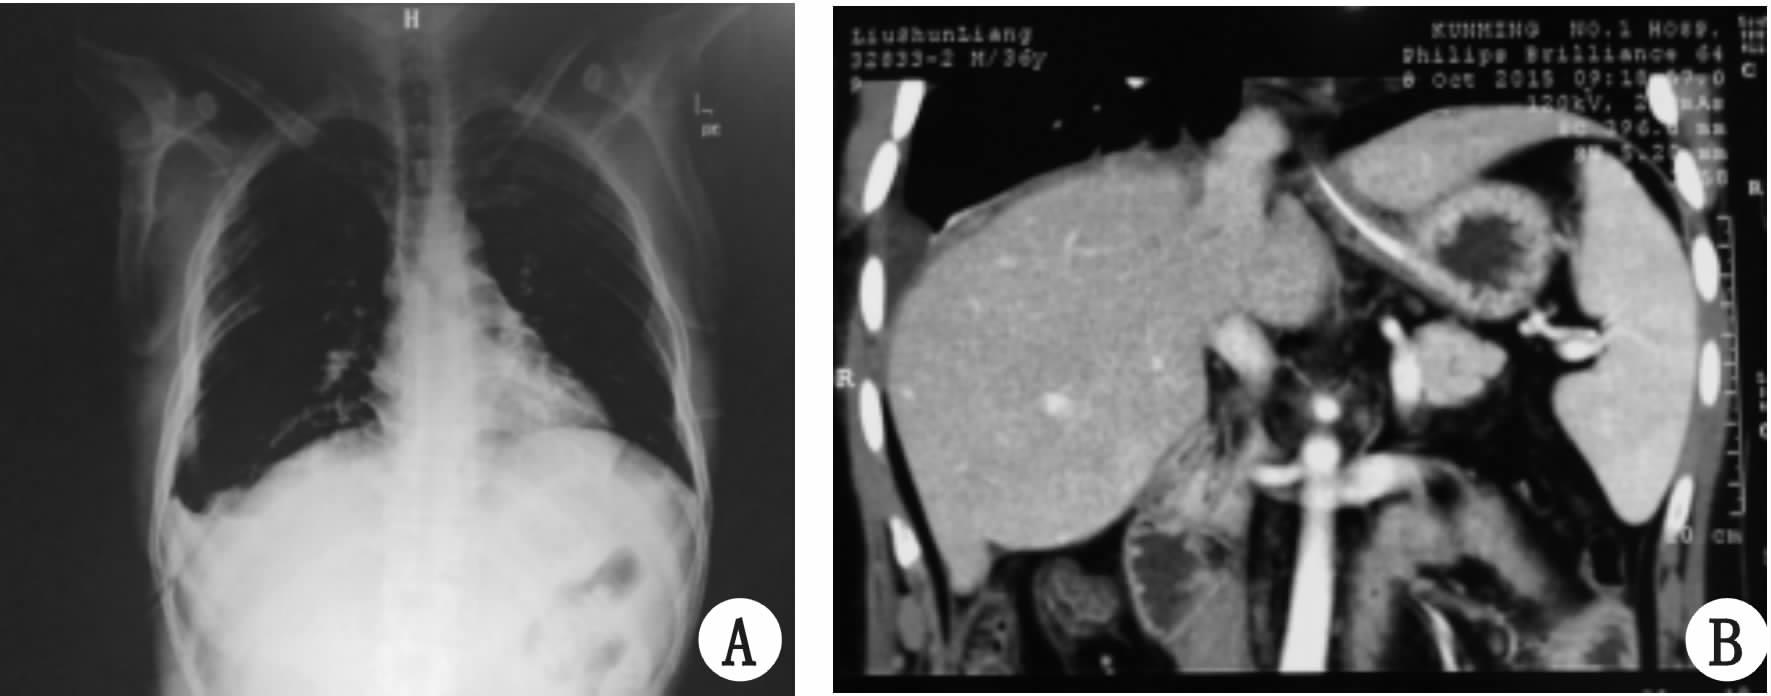

患者男性,35岁,就诊前12 h夜间睡觉时无明显诱因突发右上腹部疼痛不适入院,期间感胸闷,平卧时呼吸困难,无呕吐,腹痛前短期内无剧烈撞击史,15年前高空坠落后致胸部闭合性多发伤,血气胸,曾行右侧胸腔闭式引流。入院查体:呼吸浅快,右肺呼吸音未闻及,语颤减弱,腹软,右上腹空虚,剑突下及右侧中上腹部压痛、轻反跳痛伴肌紧张,肝浊音界上移,肠鸣音弱,2 min未闻及。入院急诊胸片示,右侧膈面升高,右肺压缩,膈疝可能(图 1A)。CT示右侧上中腹内横结肠及升结肠肠梗阻表现,并右侧膈肌抬升,右侧胸腔可见肠管影,肝脏位置上移、右肺膨胀不全,纵膈左偏,右肺压缩约80%(图 1B)。诊断为:肠梗阻,膈疝,遂急诊行剖腹探查术。

图 1 术前胸片(A)和CT结果(B)